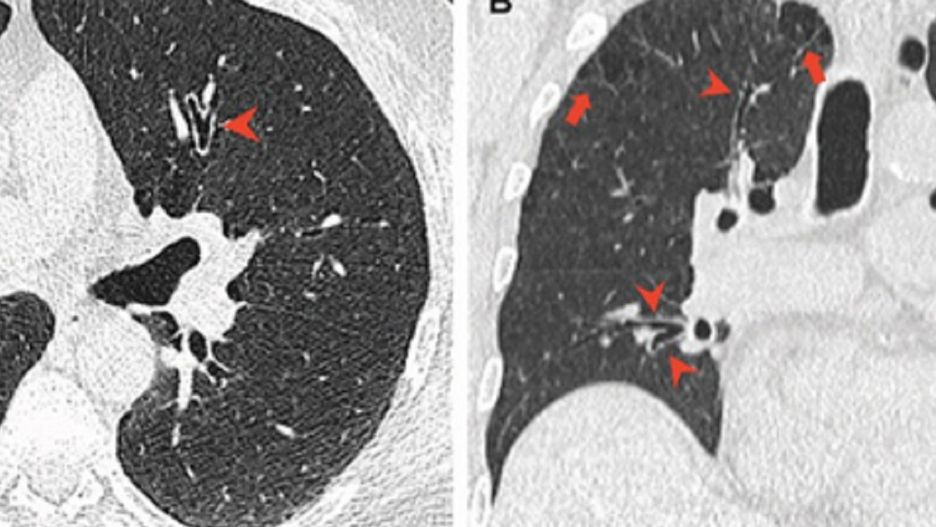

Konopie indyjskie mogą wyrządzić więcej szkód płucom i drogom oddechowych palacza niż tytoń. Tak wynika z kanadyjskiego badania opublikowanego we wtorek przez naukowców w Ottawie.

Nad szkodliwym wpływem palenia marihuany na płuca zastanawiał się prawdopodobnie każdy regularny konsument konopi. Czy lecznicze właściwości rośliny mogą rekompensować szkodliwość powstających w procesie spalania związków? Nad tym tematem pochylili się naukowcy z University of Ottawa i szpitala w Ottawie.

Wszyscy przyjrzeli się skanom rentgenowskim klatki piersiowej 56 palaczy konopi indyjskich, 57 skanom osób niepalących i wynikom 33 osób, które paliły tylko tytoń w latach 2005-2020.

Zarówno palacze tytoniu, jak i marihuany, mają nadmiernie napompowane płuca, jednak palacze marihuany mają średnio większą objętość płuc i niższe tempo transferu gazu. Oznacza to, że palacze marihuany są narażeni na komplikacje płucne, zwłaszcza, jeśli palą oni również tytoń.

Lekarze stwierdzili, że wskaźniki zapalenia dróg oddechowych i rozedmy płuc, czyli przewlekłej choroby, są wyższe wśród regularnych palaczy konopi, niż u osób, które palą tytoń lub całkowicie odrzucają marihuanę oraz tytoń.